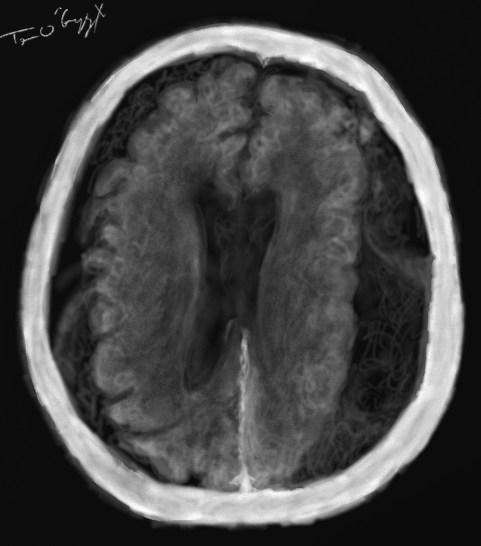

hematome sous dural

hematome sous-dural chronique bilatéral vu au scanner

Hématome sous-dural aigu et chronique